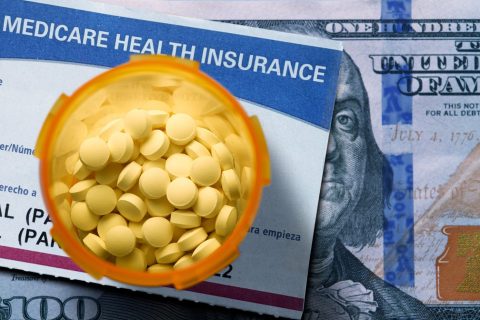

Health Federal drug price reforms are working, study says Medicare beneficiaries skipping fewer medications due to cost Beth Israel Deaconess Medical Center Communications March 13, 2026 4 min read More